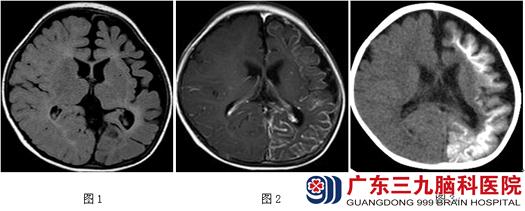

患儿张某,男,1岁4个月,10公斤,因“发作性意识障碍伴右侧肢体抽搐1年2月”入院。母孕期正常,母亲体型小给予剖宫产。出生时有可疑缺氧,哭声小。出生后家长发现左侧肢体活动较右侧明显少。2月龄时开始出现发作性眨眼,双眼向右上方斜视,右侧口角抽搐,右侧肢体不自主抖动,持续约2-3分钟。发作以睡眠时期多见。1岁时患儿开始出现“轻型发作”,表现为发呆、双眼向前或向右凝视,持续约1分钟。发作频率:1-2个月一次发作期,每个发作期1-2天,每日达十余次;入院前半个月发作明显增多,每日均发作2-3次,严重时达10余次。曾服德巴金、奥卡西平、妥泰等多种抗癫痫药物治疗,效果不佳。术前查体:入院时不能站立,不能言语,生长发育迟缓,右侧上、下肢肌力3级,右手握力差,自主活动明显较左侧少,左侧肢体肌力正常。脑电图可见左侧半球癫痫样放电。MRI:1.(MRI T2Flair序列) 左侧大脑半球脑组织萎缩,脑沟明显增宽(图1)。2.增强MRI扫描见脑回指状增强(图2)。3. CT平扫显示左侧大脑半球多脑回高密度影,提示左侧大脑半球严重钙化(图3)。3.治疗经过:患儿诊断脑面血管瘤病(III型),于2015年9月行左侧大脑半球切除术,术后给予常规治疗后好转出院。(术中见图-4、图-5、图-6),术后复查头颅MRI结果如图(图7)。